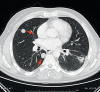

Introduction: Autopsy studies of persons who died of cancer have shown the lungs to be the sole site of metastasis in about 20% of cases. The resection of pulmonary metastases is indicated for palliative purposes if they contain a large volume of necrotic tumor, infiltrate the thoracic wall to produce pain, or cause hemoptysis or retention pneumonia. Metastasectomy with curative intent may be indicated for carefully selected patients.

Results: No prospective comparative trials have been performed to date that might provide evidence for prolongation of survival by pulmonary metastasectomy; nor have there been any randiomized, controlled trials yielding evidence that would assist in the decision whether to treat pulmonary metastases with surgery, radiotherapy, or chemotherapy (or some combination of these). The indication for surgery is a function of the histology of the primary tumor, the number and location of metastases, the lung capacity that is expected to remain after surgery, and the opportunity for an R0 resection. Favorable prognostic factors include a long disease-free interval between the treatment of the primary tumor and the discovery of pulmonary metastases, the absence of thoracic lymph node metastases, and a small number of pulmonary metastases. The reported 5-year survival rates after pulmonary metastasectomy, depending on the primary tumor, are 35.5% to 47% for renal-cell carcinoma, 39.1% to 67.8% for colorectal cancer, 29% to 52% for soft-tissue sarcoma, 38% to 49.7% for osteosarcoma, and 79% to 94% for non-seminomatous germ-cell tumors. For the latter two types of tumor, chemotherapy is the most beneficial form of treatment for long-term survival.

Conclusion: When there is no good clinical alternative, the resection of pulmonary metastases can give some patients long-lasting freedom from malignant disease. Patients should be carefully selected on the basis of clinical staging with defined prognostic indicators.